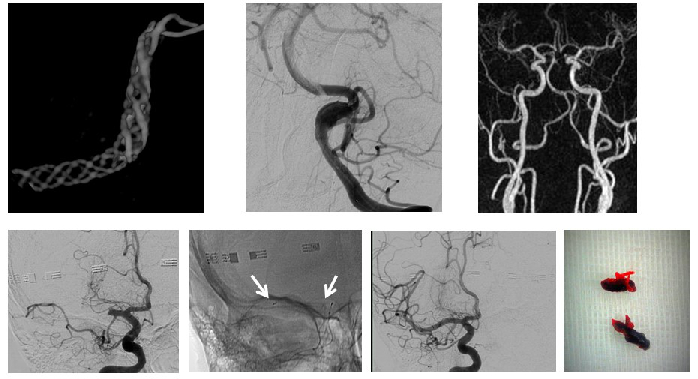

To a large extent, neuroradiological research is connected with and driven by its clinical partners (Neuro-Focus at MUI) as well as other departments (clinical and theoretical) at MUI, MCI, UMIT and LFU. Projects generated within Neuroradiology focus mostly on technical developments (dose reduction / dual-energy CT, MRI sequence and post-processing developments, fMRI/VBM, multi-nuclear MRI), some in cooperation with the Department of Radiology. Furthermore, Neuroradiology conducts clinical studies, e.g. into neurovascular disease (Fig. 1).